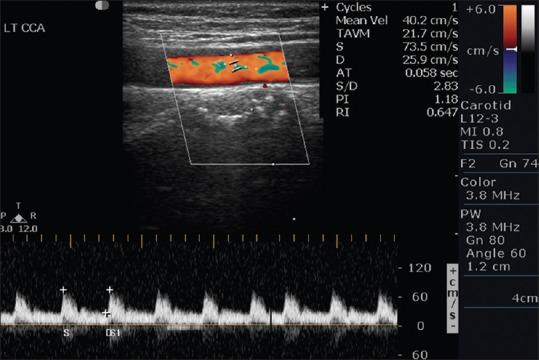

Cerebral ischemic stroke is life-threatening and debilitating neurological disease, it is the third leading cause of death in the world. Studies have shown that there is a close relationship between carotid artery stenosis and ischemic cerebral vascular disease. This study is done to assess the carotid arteries with the help of color Doppler sonography and to correlate cerebrovascular accidents.

The prospective study was carried out on 50 patients using purposive sampling technique. Risk factors such as hypertension, diabetes mellitus, smoking, and family history were documented. The data gathered from color Doppler examination consisted of peak systolic velocity of common carotid artery (CCA) and internal carotid artery (ICA), velocity ratios between CCA and ICA and plaque characteristics as seen on real-time image.

Color Doppler examination is an economic, safe, reproducible, and less time-consuming method of demonstrating the cause of cerebrovascular insufficiency in extracranial carotid artery system and will guide in instituting treatment modalities.